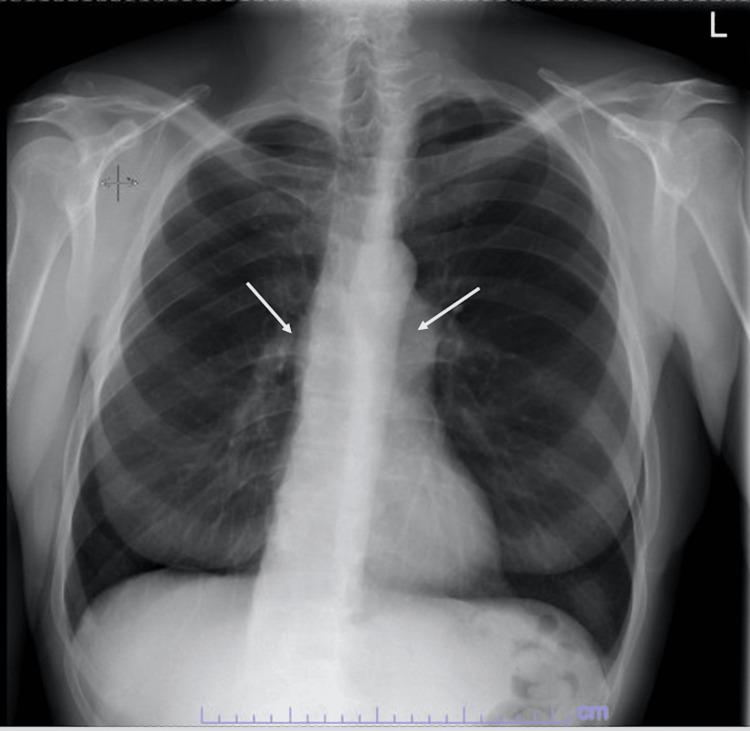

Infective endocarditis (IE) is a microbial infection affecting cardiac valves. IE most often affects the aortic valve and is commonly caused by community-acquired, penicillin-sensitive streptococcus that enters through the oral cavity. In this report, we present a case of a 66-year-old man with a medical history of congenital pulmonic stenosis status after pulmonic valve (PV) repair. The patient underwent a transesophageal echocardiogram showing a 1 cm × 0.7 cm mobile vegetation attached to the ventricular aspect of the right coronary aortic cusp and a 1.1 cm × 0.5 cm mobile vegetation attached to the arterial aspect of the PV cusp. In conclusion, concomitant right- and left-sided IE is an exceedingly rare condition. Due to its rarity and complexity of presentation, pulmonic valve endocarditis (PVE) requires a multidisciplinary approach to its perioperative management to prevent systemic complications.

感染性心内膜炎(IE)是一种影响心脏瓣膜的微生物感染。IE最常累及主动脉瓣,通常由经口腔进入的社区获得性、对青霉素敏感的链球菌引起。在本报告中,我们介绍了一例66岁男性患者,其有先天性肺动脉狭窄病史,曾接受肺动脉瓣(PV)修复术。患者接受经食管超声心动图检查,显示一个1 cm×0.7 cm的活动赘生物附着于右冠状动脉主动脉瓣叶的心室面,以及一个1.1 cm×0.5 cm的活动赘生物附着于PV瓣叶的动脉面。总之,双侧IE是一种极其罕见的情况。由于其罕见性和临床表现的复杂性,肺动脉瓣心内膜炎(PVE)需要多学科方法进行围手术期管理,以预防全身并发症。